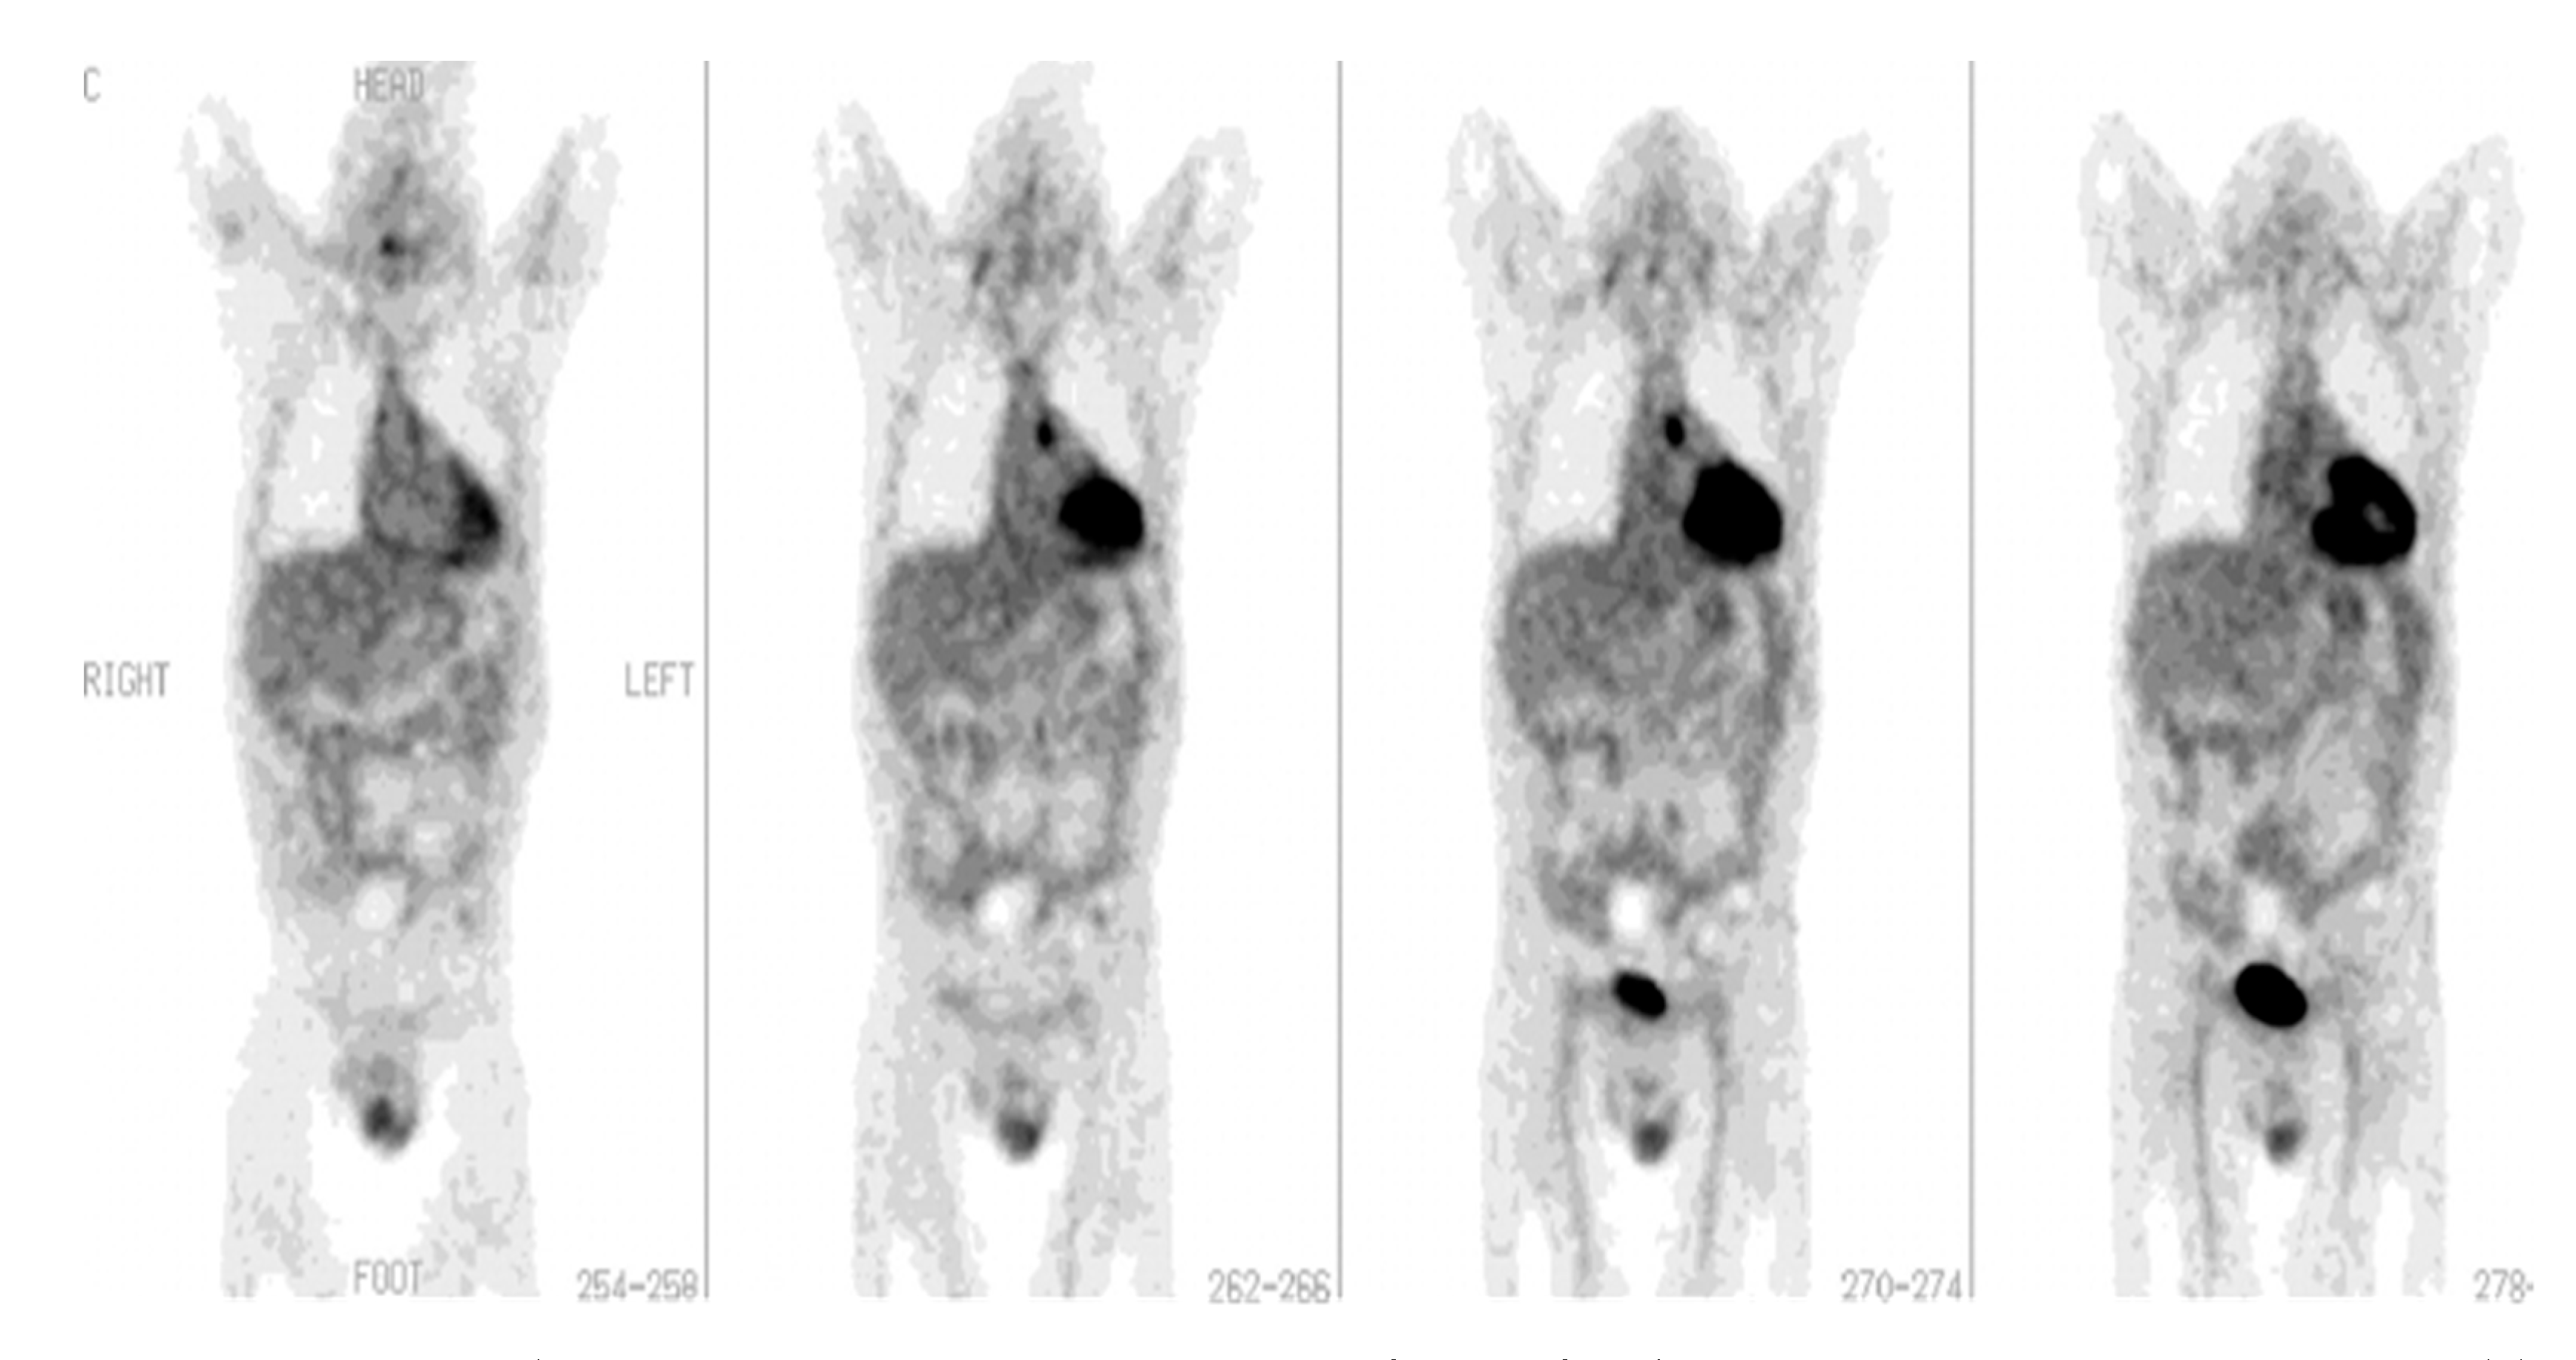

- Vind, S.H.; Hess, S. Possible Role of PET/CT in Infective Endocarditis. J. Nucl. Cardiol. 2010, 17, 516–519. [Google Scholar] [CrossRef] [PubMed]